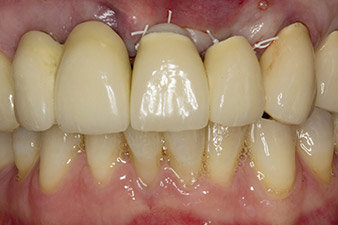

Después de la cicatrización primaria, los tejidos blandos se modelaron con ayuda del puente con base reconstruida. Dos meses después, se procedió a la exposición del área con una incisión de la cresta maxilar en sentido ligeramente palatino (figura 2).

El hueso alveolar de la posición 22 resultó tener unas dimensiones suficientes. Las figuras 2 y 4 muestran la preparación del lecho del implante, el corte de rosca y la colocación del implante con el equipo Implantmed.

orificio piloto utilizando el nuevo Implantmed y el contra-ángulo WS-56 L

Imagen 2: Dos meses después, se practicó un orificio piloto utilizando el nuevo Implantmed y el contra-ángulo WS-56 L (programa P1, transmisión 1:1). La refrigeración se realizó a través del tubo de spray colocado a la izquierda (para diestros).